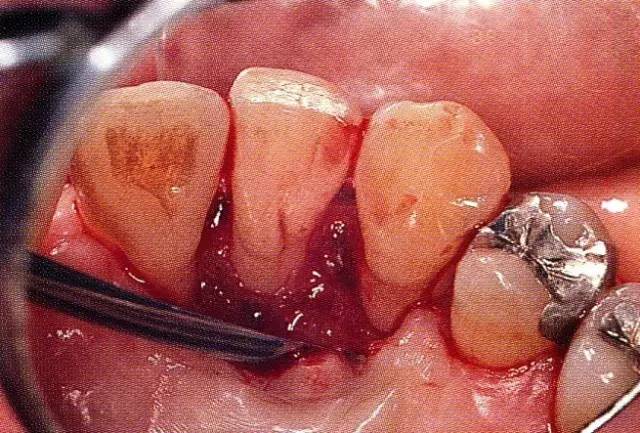

640.webp (3).jpg

▲圖7-4  術(shù)后1年2個月再翻開看的情況。與圖7-1的骨缺損狀態(tài)相比可知形成了臨床性骨再生。